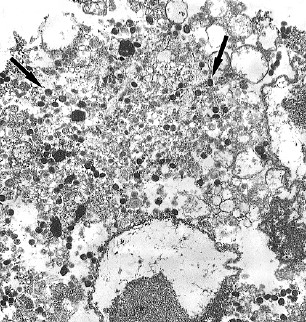

Материалы и методы. В работе использовали биологические материалы, полученные из поражённого участка кожи (содержимое везикул), мазка из носоглотки, мокроты и венозной крови пациента с подозрением на оспу обезьян. Заболевание подтверждали методом полимеразной цепной реакции (ПЦР) с последующим определением нуклеотидной последовательности вирусной ДНК методом секвенирования. Штамм ВОО из клинических образцов выделяли в культуре клеток Vero E6. Противовирусную эффективность НИОХ-14 в отношении изолята ВОО оценивали с использованием адаптированного спектрофотометрического метода.

Результаты. Диагностическое исследование биологических образов пациента, вернувшегося из туристической поездки по европейским странам, с жалобами на кожную сыпь по всему телу выявило в них ДНК ВОО. Изолят ВОО был выделен из содержимого везикулы в культуре клеток, генетическая последовательность MPXV-pustule S45 была собрана по результатам проведения высокопроизводительного параллельного секвенирования.

Заключение. В настоящем исследовании методами ПЦР в режиме реального времени, секвенирования и электронной микроскопии был выявлен и идентифицирован возбудитель оспы обезьян, из клинического образца (содержимое везикул) на культуре клеток Vero Е6 был выделен изолят ВОО и, таким образом, подтверждён первый завозной случай оспы обезьян в России. Было доказано, что препарат НИОХ-14 проявляет высокую противовирусную активность in vitro в отношении выделенного изолята ВОО.